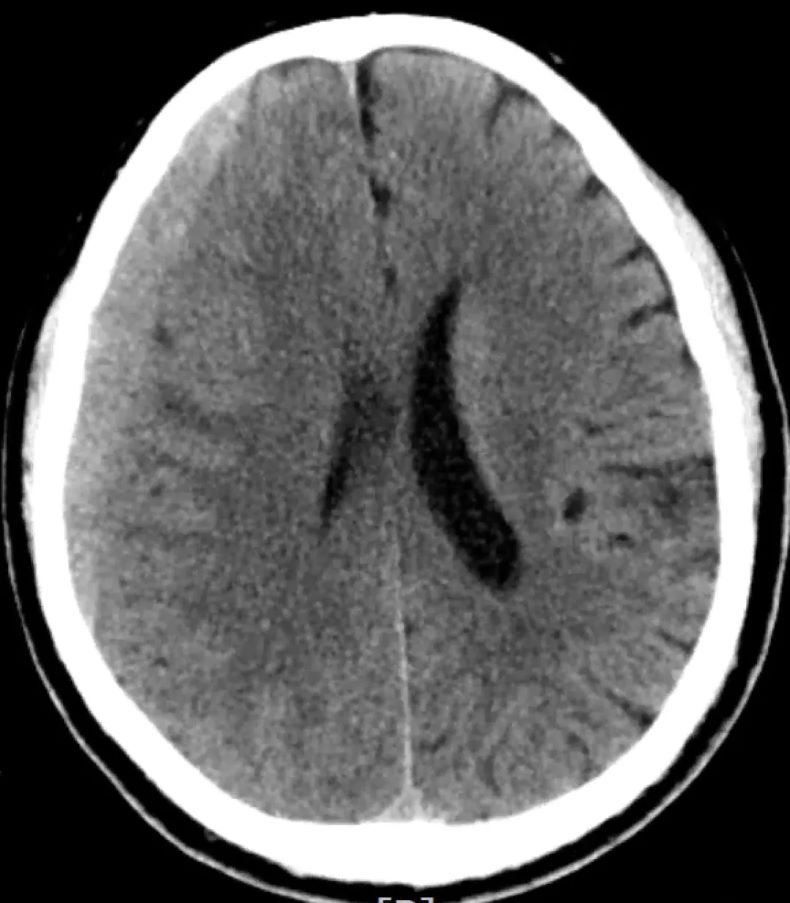

▲ 脑膜中动脉栓塞效果图

而脑膜中动脉栓塞术作为血肿“终结者”,为部分慢性硬膜下血肿患者和复发性急性硬膜下血肿患者带来了新的希望。这一技术通过精准的介入手段,通过导管将微小的栓塞材料精准输送到脑膜中动脉,阻断其向血肿区域的供血,使血肿逐渐自然吸收。

大家可以把脑膜中动脉想象成给血肿“输送养分”的通道,一旦通道被阻断,血肿就会因为缺乏“养分”而逐渐萎缩、消失,从而达到治疗的目的。